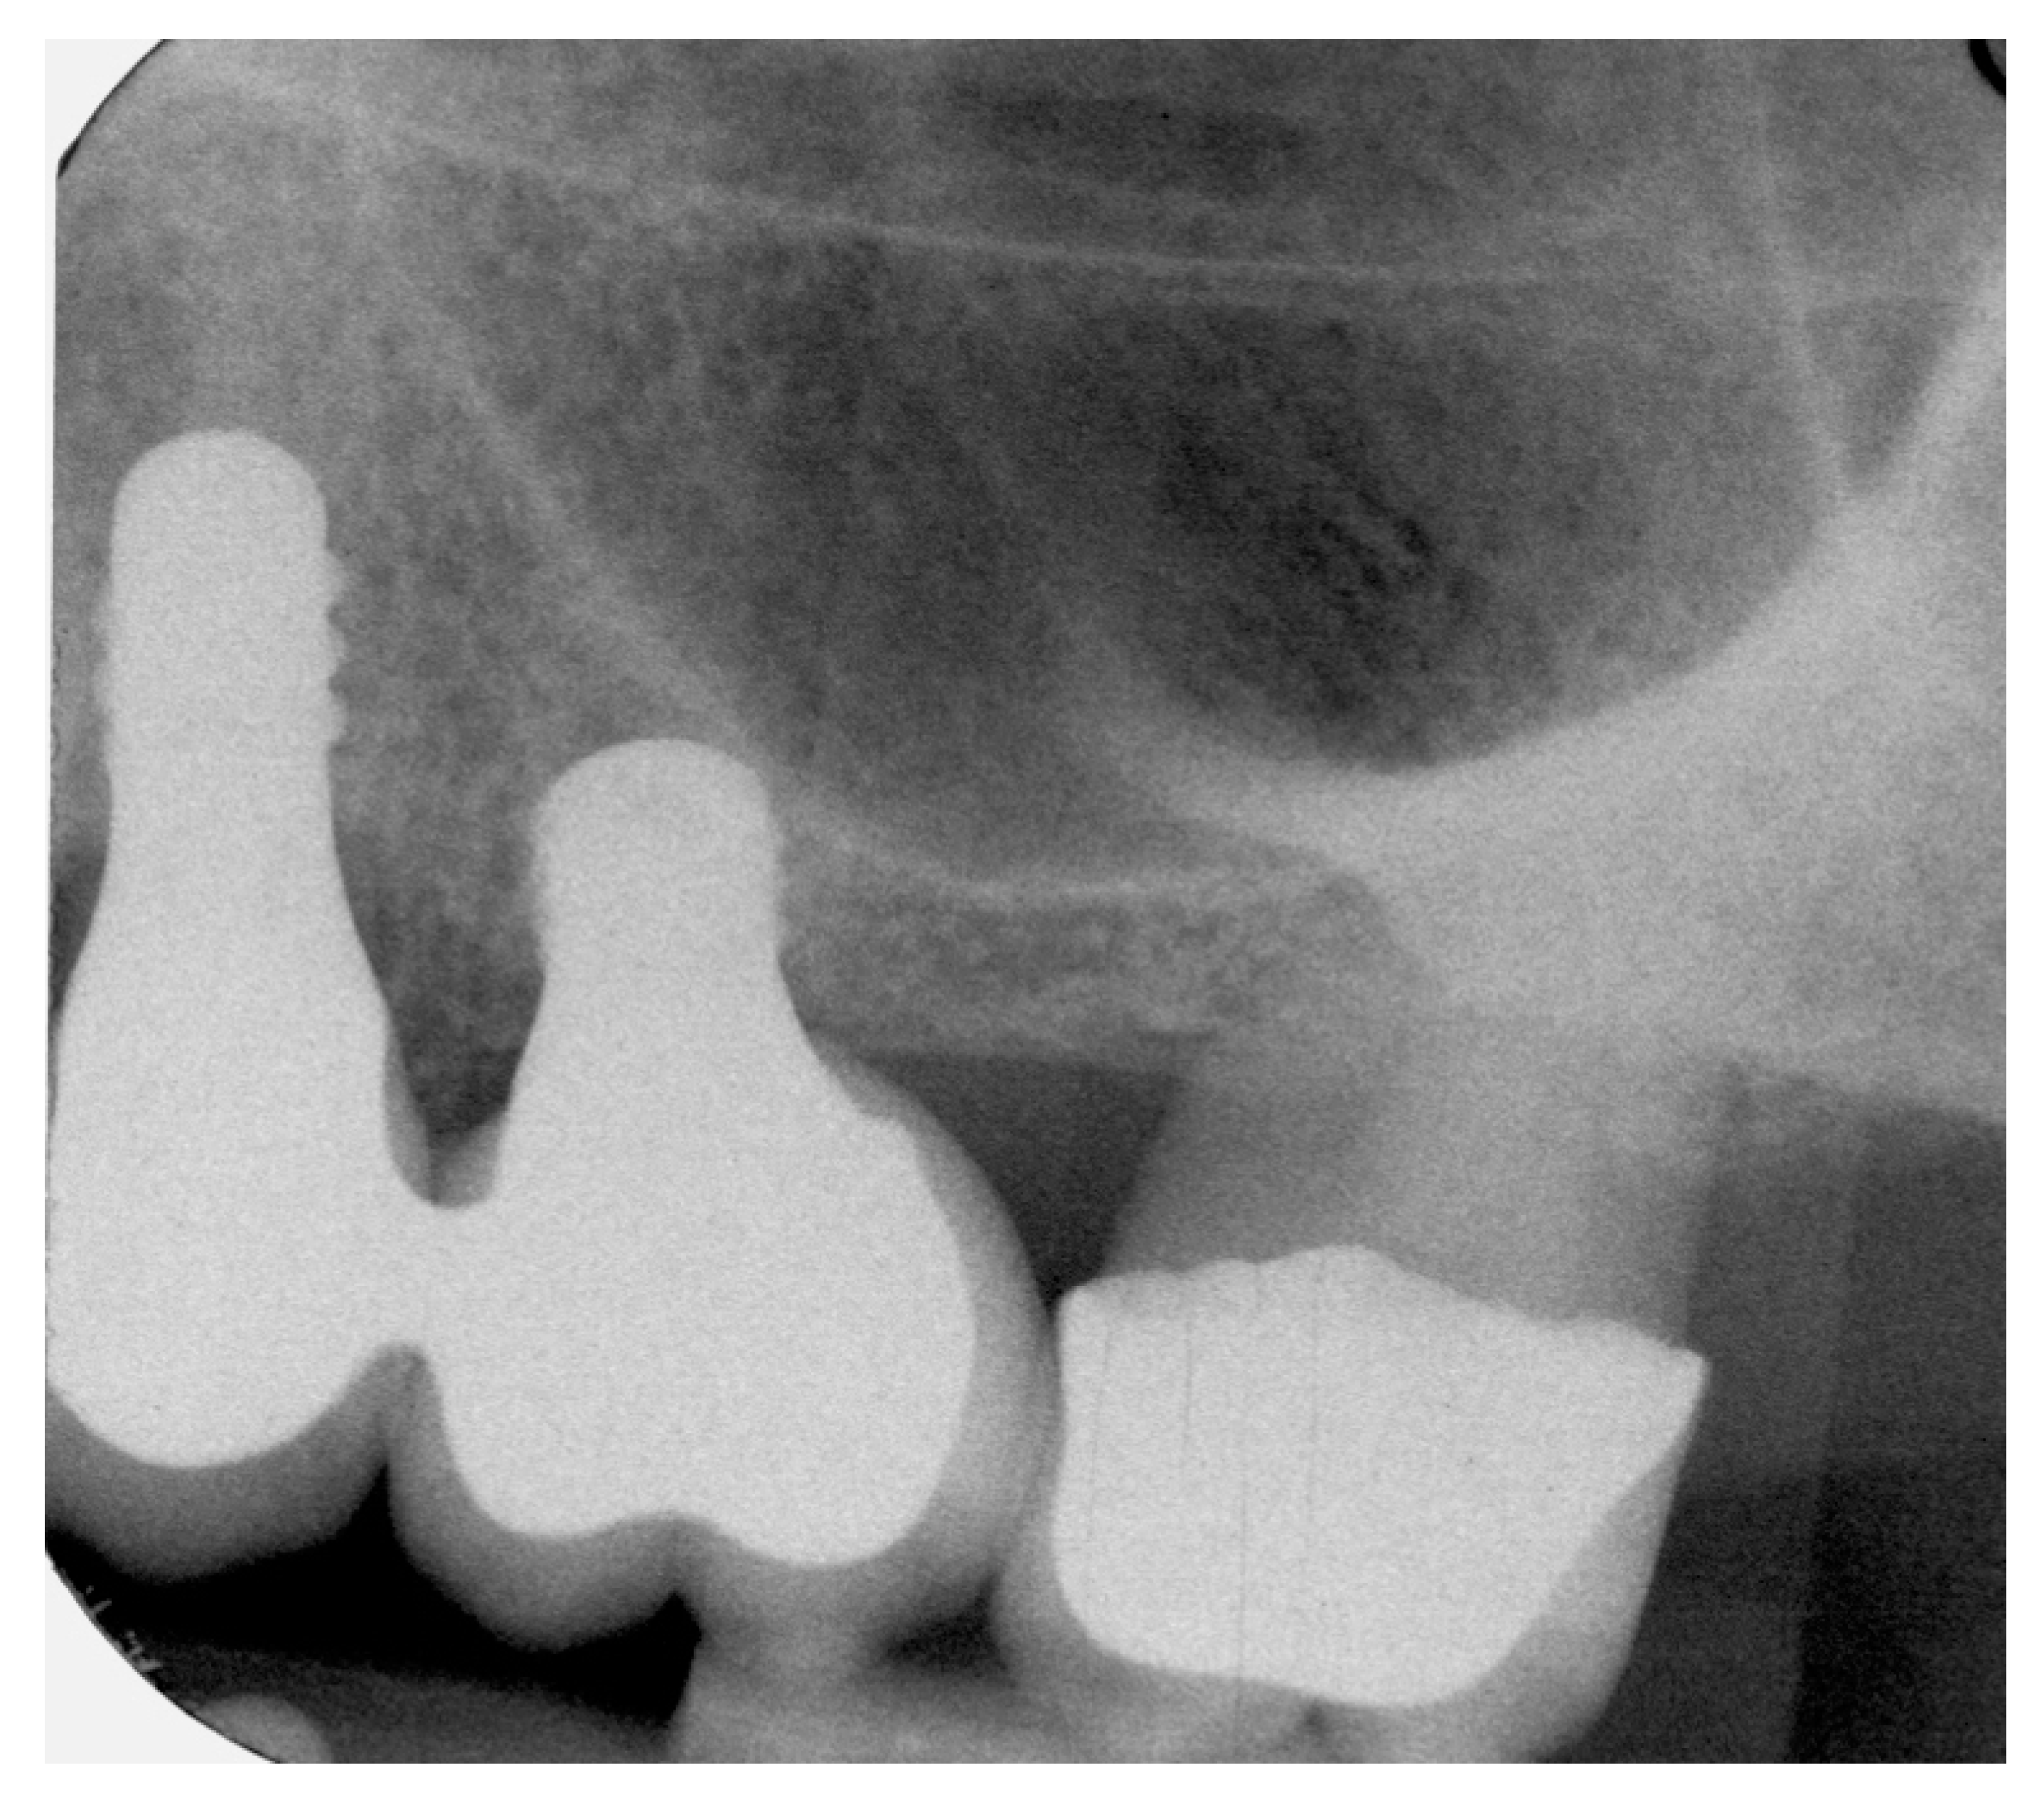

4.1. Marginal Bone Level (MBL)

4.2. Bone tissue remodeling (MBL change)